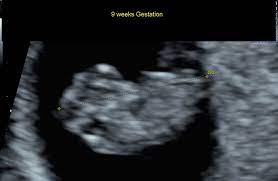

10 Weeks Pregnant Ultrasound, My Ultrasound At 10 Weeks Pregnant Baby Hardnett 2016 Youtube - Bloating can still be a contributor to a perceived bump and not everyone will see a baby bump at 10 weeks.. Pregnancy week 10 learn what is happening with your baby's development in week 10. At 10 weeks pregnant, you're getting close to the end of your first trimester. At this stage, the baby is growing even more rapidly! So, there's a chance that you've either already had the ultrasound, or that you'll be having it soon. You are 10 weeks and 2 days pregnant.

But if you are feeling some uncomfortable symptoms, things may seem like they're dragging. You are 11 weeks exactly pregnant. An ultrasound scan at this stage would show your baby making little, jerky movements. Your 10 weeks pregnant belly. A guide on pregnancy at 10 weeks with information on what to expect, baby development, and symptoms. You are 10 weeks and 2 days pregnant. Meanwhile, your baby is growing and hitting a big milestone at the end of this week. In the 10 weeks pregnant ultrasound, you would notice that your baby's body parts are now visible more clearly.

A guide on pregnancy at 10 weeks with information on what to expect, baby development, and symptoms. Meanwhile, your baby is growing and hitting a big milestone at the end of this week. At 10 weeks of pregnancy, the foetus weighs about 4gm and measures around 3.1cm from crown to rump. The cvs (chorionic villus sampling), performed between weeks 10 and 13, uses an ultrasound to determine the placenta's location. Plus, find out what to expect at your first ultrasound , and why you may be experiencing the pregnancy glow. Avoid wearing tight and constricting clothes. You are 10 weeks and 2 days pregnant. At this stage, the baby is growing even more rapidly! Either way, at ten weeks pregnant, you are about a quarter of the way through your pregnancy. So, there's a chance that you've either already had the ultrasound, or that you'll be having it soon. Bereichern sie ihr leben durch unvergessliche yoga erlebnisse. Just was told no lifting, no sex, and no other strenuous work until approved by doctor. But if you are feeling some uncomfortable symptoms, things may seem like they're dragging.

You may be wondering when those pesky early pregnancy symptoms will start to fade or getting ready to share your big news with the world. This device is kind of like a microphone placed on the belly. Pregnancy symptoms & belly pictures. But if you are feeling some uncomfortable symptoms, things may seem like they're dragging. Ultrasounds are usually done in the first trimester to confirm a viable pregnancy, confirm the heartbeat, and confirm molar or ectopic pregnancies and also to assess abnormal gestation. A month later hemmorage healed on it own and was back to normal activity. 10 weeks 3 days pregnant. Ultrasound image of identical twins at 10 weeks, these babies share the same sac. By conducting a scan, she will be able to identify whether or not your baby is developing normally. Avoid wearing tight and constricting clothes. Pregnancy week 10 learn what is happening with your baby's development in week 10. His toes and fingers have taken a distinct form and started developing fingernails as well. At 10 weeks of pregnancy, the foetus weighs about 4gm and measures around 3.1cm from crown to rump.